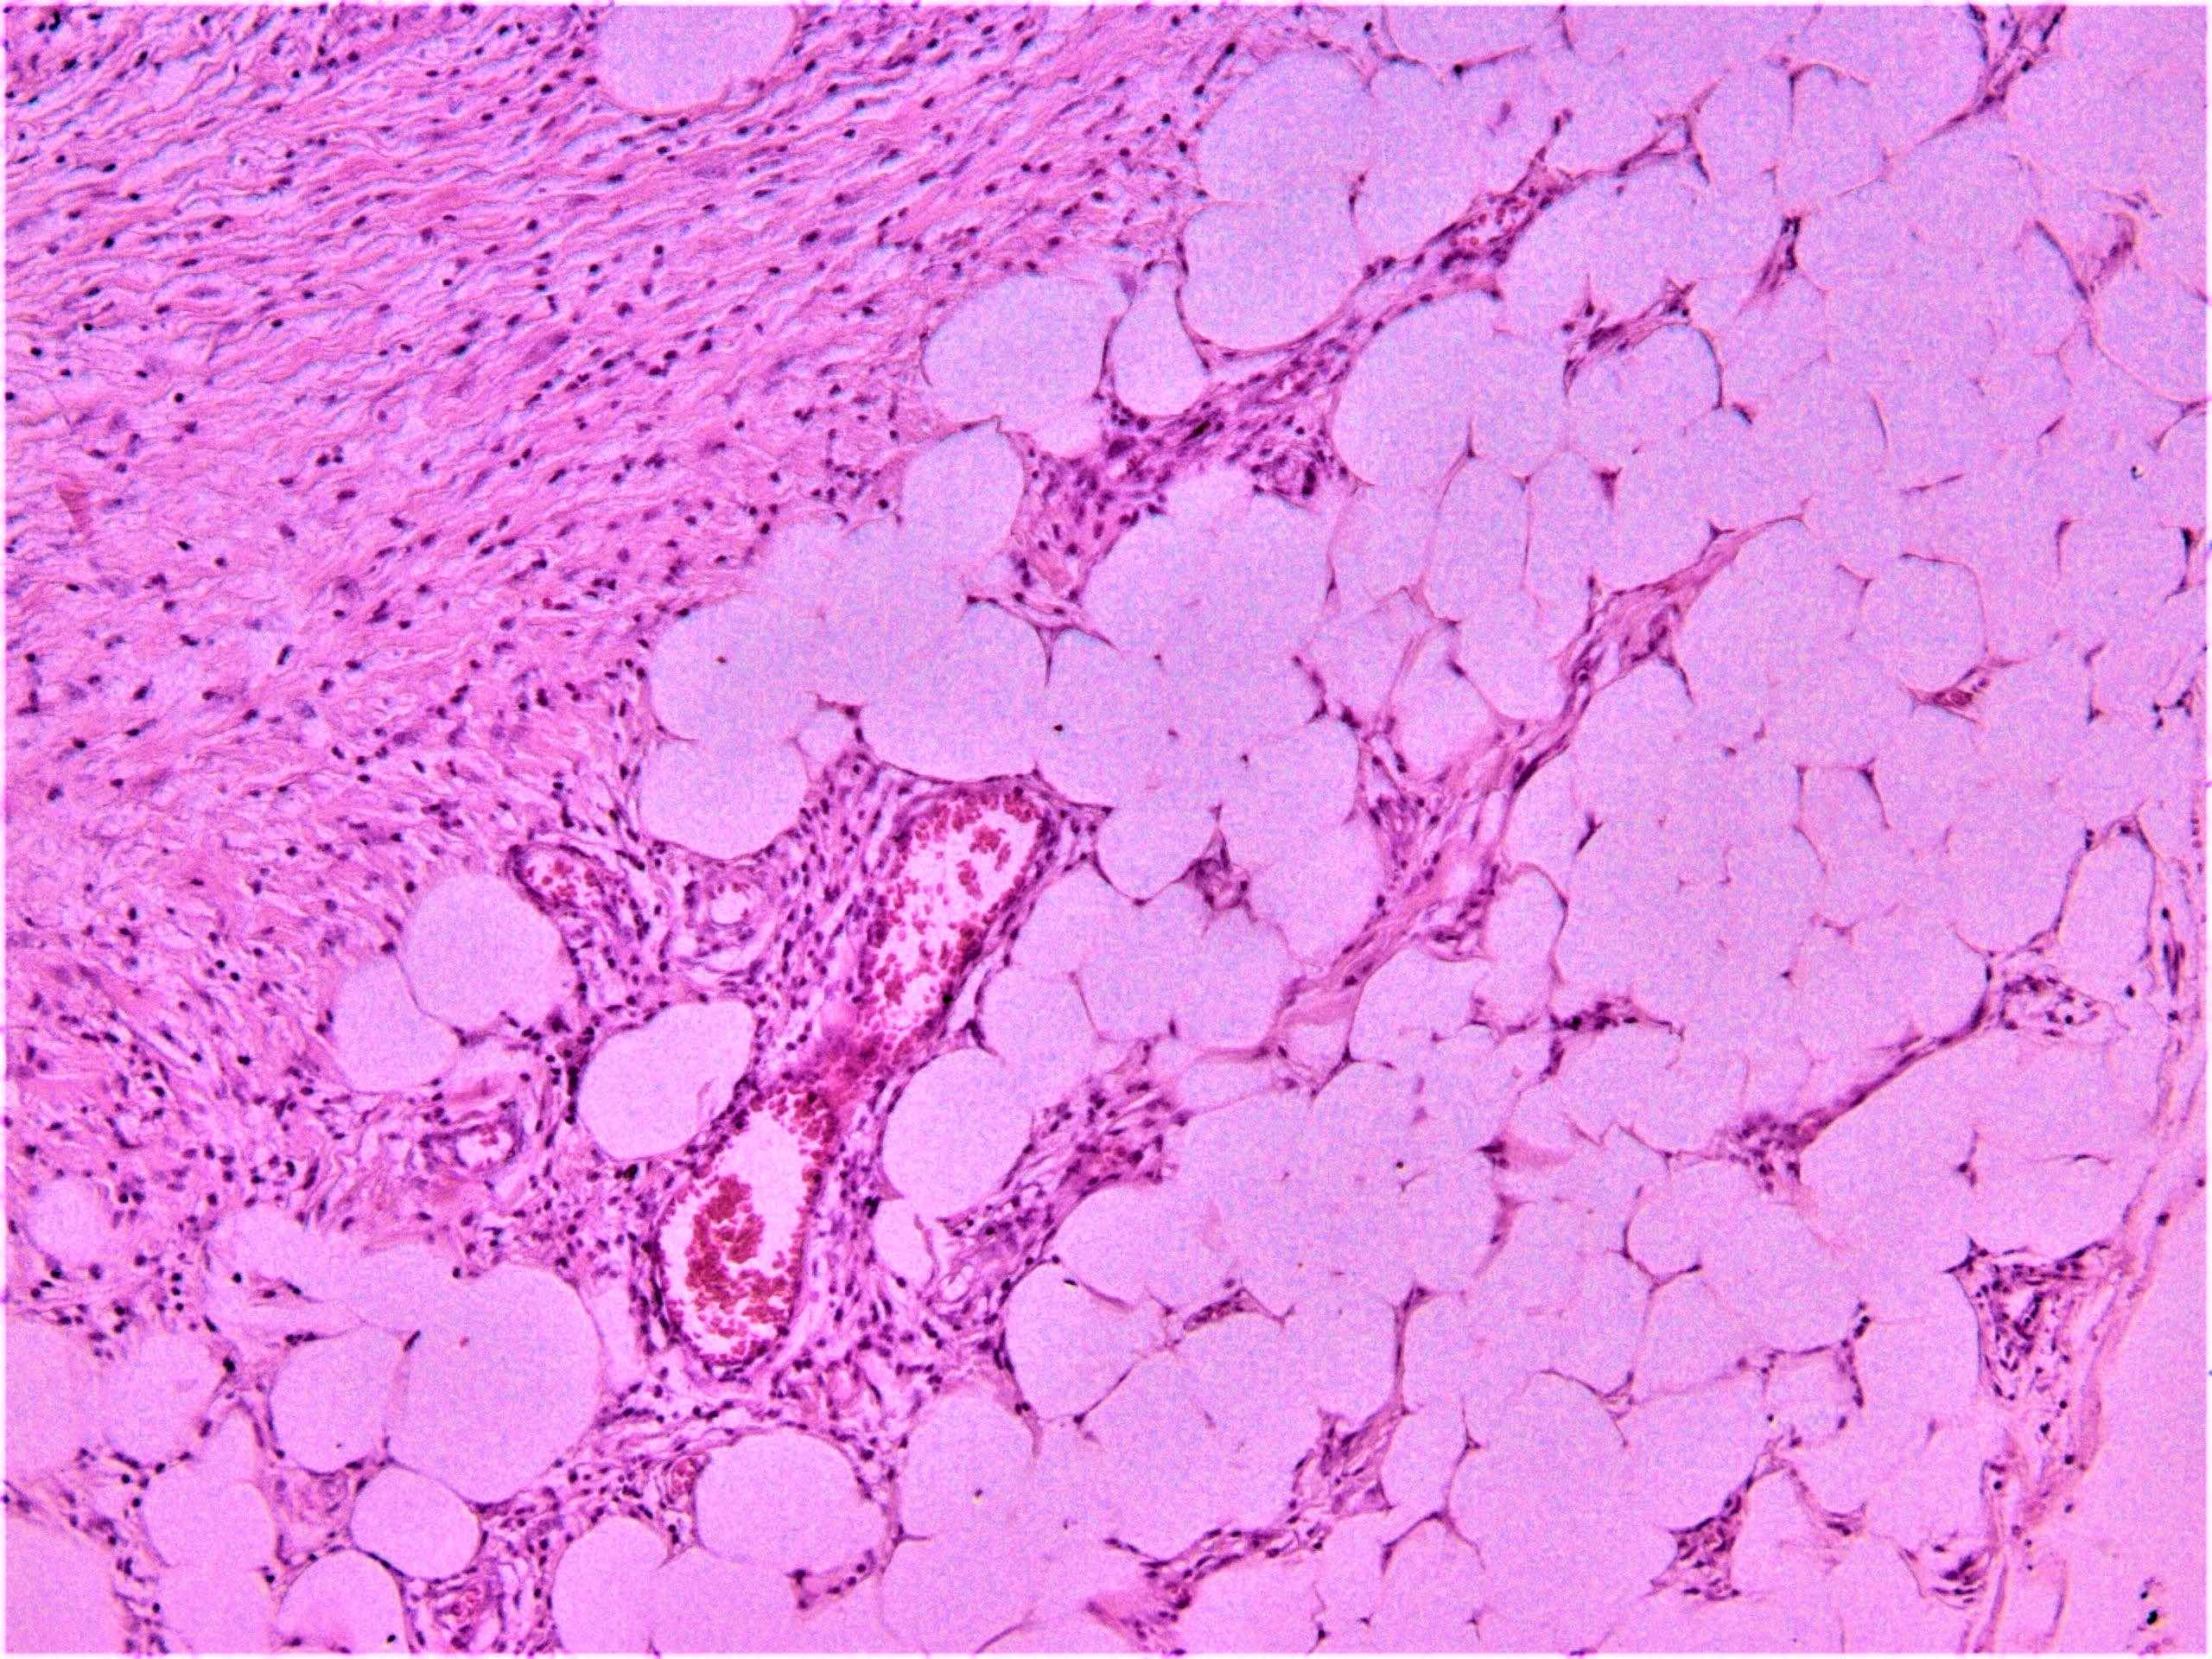

Microscopic (histologic) description

- Erythema nodosum-like lesions: septal panniculitis; vasculitis (lymphocytic or neutrophilic) and necrobiosis may be found

Microscopic (histologic) images

Sample pathology report

- Right leg, erythematous subcutaneous nodule, incisional biopsy:

- Erythema nodosum-like lesion (given the history, compatible with Behçet disease) (see comment)

- Comment: Septal panniculitis with unremarkable epidermis. Dermis shows moderate perivascular lymphocytic infiltrate. The subcutaneous fat demonstrates widening of the fibrous septa with edema and infiltration of lymphocytes and histiocytes. Spillover of infiltrate to the adjacent fat lobules is present. Small focus of lymphocytic vasculitis is noted.